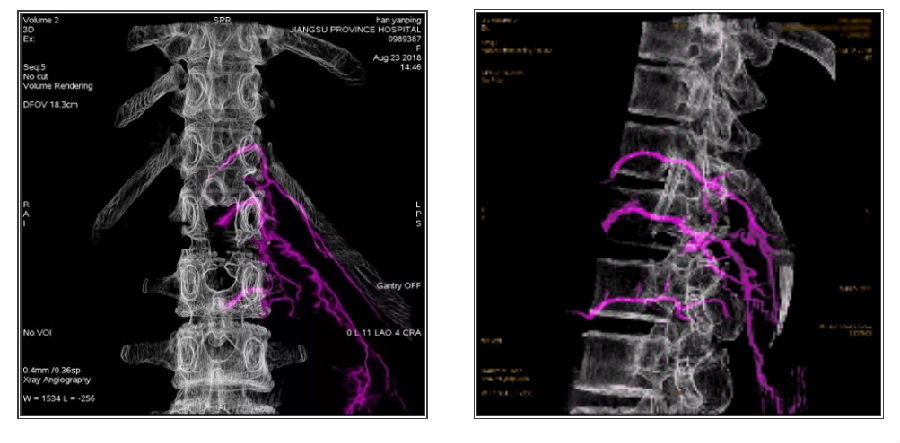

影像融合技术在脑脊髓血管病中探索及创新